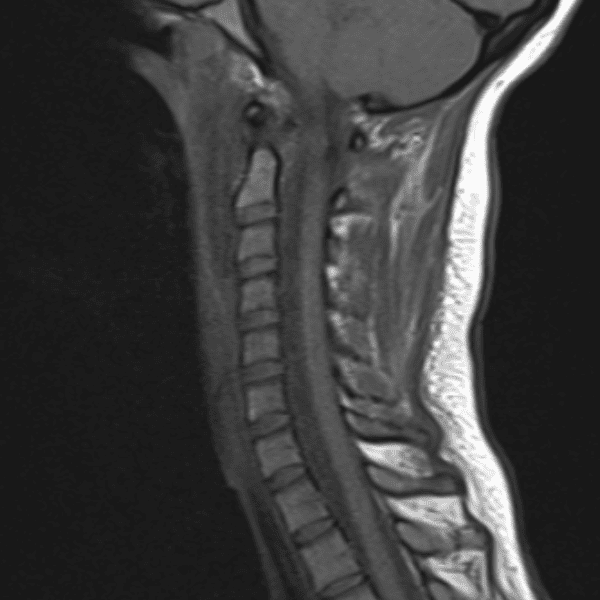

Simulates call by including subtle or difficult cases and some normals.

35 cases